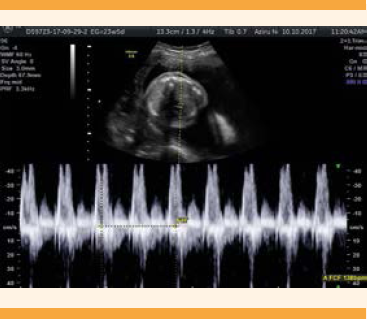

Paciente de 27 años, primigesta. El primer ultrasonido reportó: embarazo gemelar, monocorial, biamniótico, de 14 semanas de gestación, con feto A vivo, sin alteraciones estructurales. El feto B: acárdico, anencefálico, con una masa ovalada ecogénica, con edema subcutáneo y miembros superiores e inferiores, con flujo en el cordón umbilical. El segundo ultrasonido (Figuras 10, 11 y 12) reportó: embarazo gemelar, monocorial, biamniótico, de 15.5 semanas de gestación, con gemelo acárdico. Feto A con fetometría acorde con las semanas de amenorrea, ausencia de reflujo tricuspídeo. Feto B acárdico, acéfalo, de 13.3 semanas de gestación, flujo intermitente en el cordón umbilical. A las 18 semanas de gestación se realizó, en el Hospital Universitario Dr. José Eleuterio González, coagulación láser del cordón umbilical del feto acárdico, sin dificultades técnico-quirúrgicas. La paciente se hospitalizó a las 19.3 semanas de gestación por amenaza de aborto e infección de vías urinarias, tratada con antibiótico e indometacina. El servicio de Medicina materno fetal reportó que se trataba de un embarazo gemelar de 18.6 semanas, con feto acárdico, fetometría 5 días menor a las semanas de amenorrea. Los ventrículos laterales se advirtieron aumentados, sin otros marcadores para cromosomopatías del segundo trimestre, con líquido amniótico aumentado. A las 19.3 semanas de embarazo tuvo ruptura prematura de membranas y, posteriormente, expulsión de ambos fetos; el feto A, masculino de 260 g, el feto B, sin cráneo, solo tronco y extremidades inferiores. La paciente fue dada de alta del hospital, sin complicaciones.

Figura 10 Caso 4: Ultrasonido pélvico de embarazo gemelar monocorial biamniótico de 15.5 semanas de gestación con gemelo acárdico. Feto A con fetometría acorde con las semanas de amenorrea, sin estructuras aparentes, ausencia de reflujo tricuspideo, flujo de la arteria umbilical morfológicamente con índice de resistencia, normal. Feto B: acárdico, acéfalo, de 13.3 semanas de gestación.